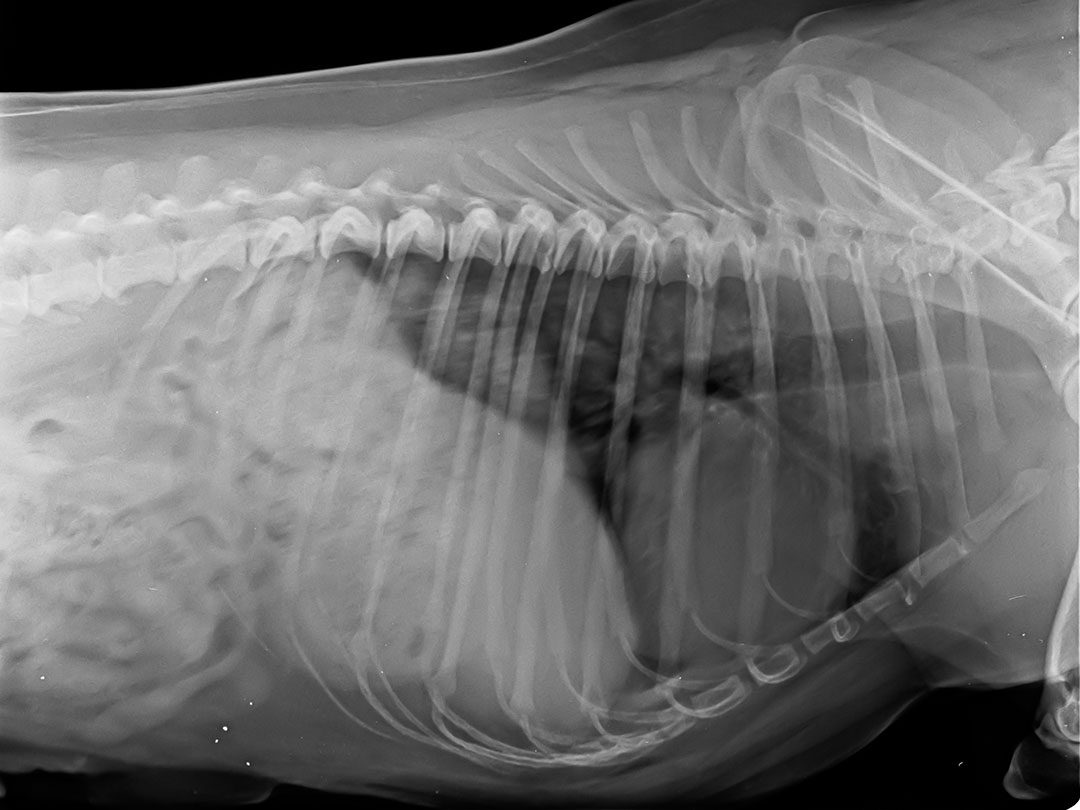

x-ray of a dog's lungs and heart

Rapid X-Ray Results

Digital X-rays are one of the most effective tools we use to evaluate your pet’s bones, joints, and internal organs. At our Holmdel animal hospital, our digital X-ray system allows us to:

Digital radiology can help diagnose broken bones, arthritis, heart disease, pneumonia, bladder stones, tumors, and other conditions. Because results are available instantly, we can move forward with treatment sooner, keeping your pet more comfortable.